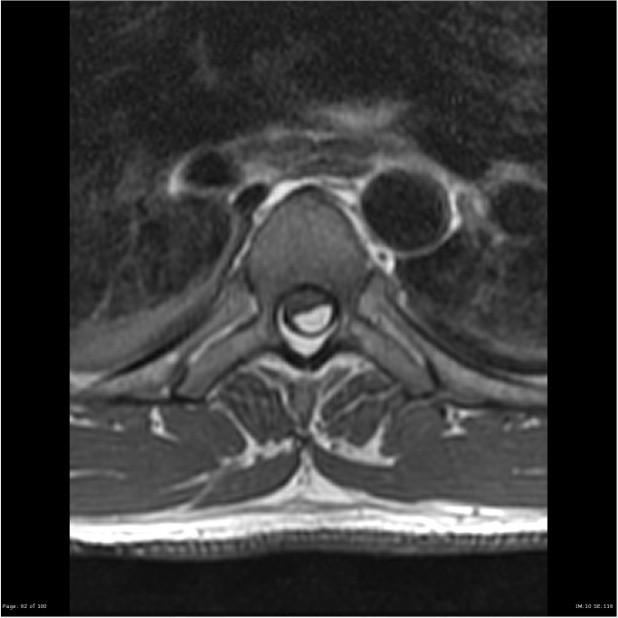

THICKENED FILUM FIBROLIPOMA OF THE FILUM TERMINALE

• Normal Filum > 1mm at L5-S1, axial plane, similar to adjacent nerve roots

• Conus may be normal or low in position

Watch for loss of the normal “pointy: conus or abnormal posterior “tethered” look to the filum at the conus

Chemical shift of fat on PD/T2